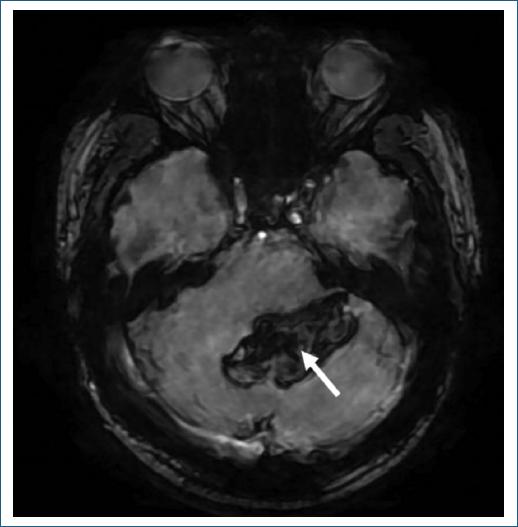

A su ingreso presentaba presión arterial de 110/80 mmHg, 88 lpm y 16 rpm. Al examen neurológico mostraba somnolencia, disartria escándida, dismetría y disdiadocosinesia de las cuatro extremidades, maniobra de Stewart-Holmes presente bilateral y rigidez de nuca; el resto de la exploración sin otros hallazgos patológicos. Se realizó tomografía computarizada (TC) de cráneo que corroboró una HIC involucrando el parénquima cerebeloso con predominio vermiano y en el hemisferio izquierdo, con un volumen estimado de 14 ml. Asimismo, se acompañaba de irrupción al espacio subaracnoideo, condicionando obliteración del IV ventrículo, sin requerir intervención quirúrgica. Durante su estancia se realizaron resonancia magnética (Fig. 1), angio-TC y angiografía diagnóstica por sustracción digital, sin evidencia de anomalía vascular estructural ni de lesiones parenquimatosas que sugirieran alguna causa de la HIC (Fig. 2). A su egreso el paciente persistió con dismetría en el hemicuerpo izquierdo, cuya mejoría sintomática le ha permitido el retorno a su actividad laboral.